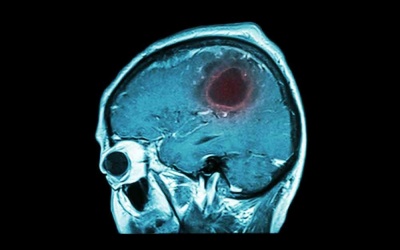

Xuất huyết giảm tiểu cầu là căn bệnh khá nguy hiểm. Nếu không phát hiện sớm các triệu chứng và điều trị kịp thời có thể dẫn đến xuất huyết não, thậm chí tử vong.